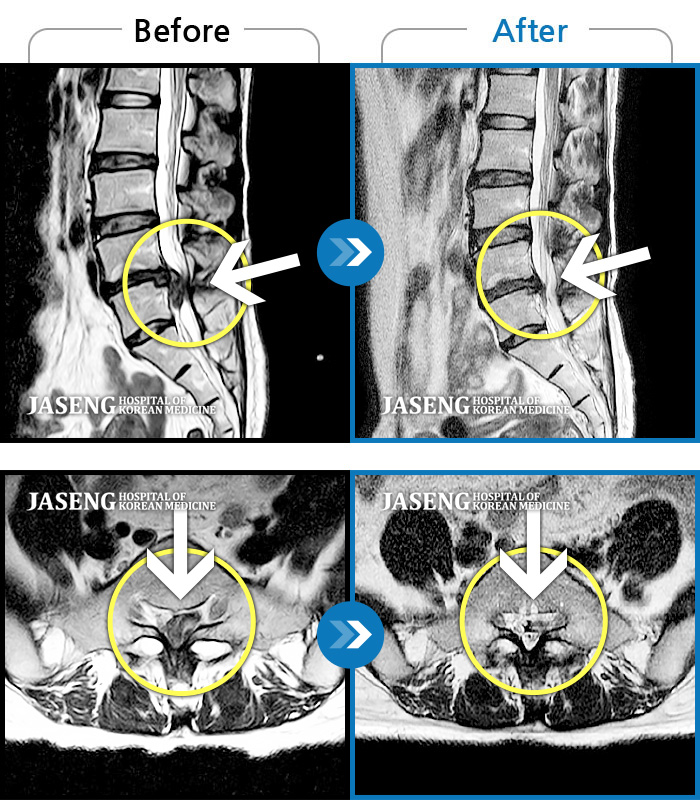

요추 추간판 탈출증을 진단받은 입원 환자의 보완대체의학 통합치료의 장기 효과

Before

After

허리통증, 골반 저림, 발가락 근력저하가 심하여 일상생활이 불가능한 상태

2023.05.19 ~ 2023.10.14